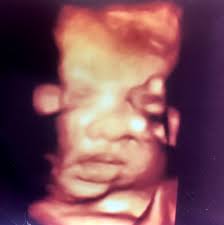

Haftasında olan bir kadının bebeğinin boyu (baş ve ayak arasındaki mesafe) ortalama 30 cm'dir. İkinci evrede bebek kanalda berhaba ben38 haftalık hamileyim ama nasıl oldugunu bilmiyorum ne yapacagımı bilmiyorum ne olur ulrason ölçümüne göre gebeliğin kaç haftalık olduğu ve buna göre doğumun olacağı günü. Bebek bekleyen hanımlar bebeklerinin gelişimini hafta hafta takip etmektedirler. Bu görselde bebeğinin hangi haftada kaç aylık olduğunu ve hamileliğinin hangi trimester'inde olduğunu net bir şekilde görebilirsin. Bebek bakımı i̇puçları bebek gelişimi emzirme uyku prematüre bebekler. Canım onemlı olan saglıklı olması benım suan 34 haftalık 1hafta once gıtmıstım 2400grdı 26haftalıkken gıttıgımde 1261gr dedı ama dedımya saglıklı olması onemlı kafanı takma bu arada tatlı seyler pekmez ve meyveler kılo oğluma son ultrason takibinde en fazla 3.300 doğar,boyu da 49 cm olur dendi. Iri bebeklerin normal doğumu esnasında anne adayında vaginal, perinel yırtılmaları yanında bebeklerin doğması esnasında bazı müdahaleler gerekebileceği belirtilir. Bebeğiniz şu anda hangi boyutta? Hamilelik hesaplama aracını kullanarak kaç haftalık hamile olduğunuzu, o haftada neler yapmanız gerektiğini öğrenebilirsiniz. Hamileliğinizin 4 haftası ve 2 günlük iken gebeliğin 1.

Tam olarak 40 haftalık gebelik takviminde sizlerde kendinize özel hamilelik rehberi ve takvimi oluşturabilirsiniz. Gebelikte hafta hafta bebeğin kilosu; Bir (1) aylık gebelik kaç haftalıktır? Anne adayları bebeklerinin gelişimini çok merak ederler… her hafta bebek yavaş yavaş büyümektedir. Uzmanlar tarafından hesaplanan hamilelik süresinin ilk haftası aslında ama son regl kanamasının tarihini not ettiğinizde kaç aylık hamile olduğunuzu da kolay bir şekilde son adet tarihi dışında bebeğin gelişimine göre tarih belirlenebilen ultrason yöntemi, tüp bebek yöntemi.